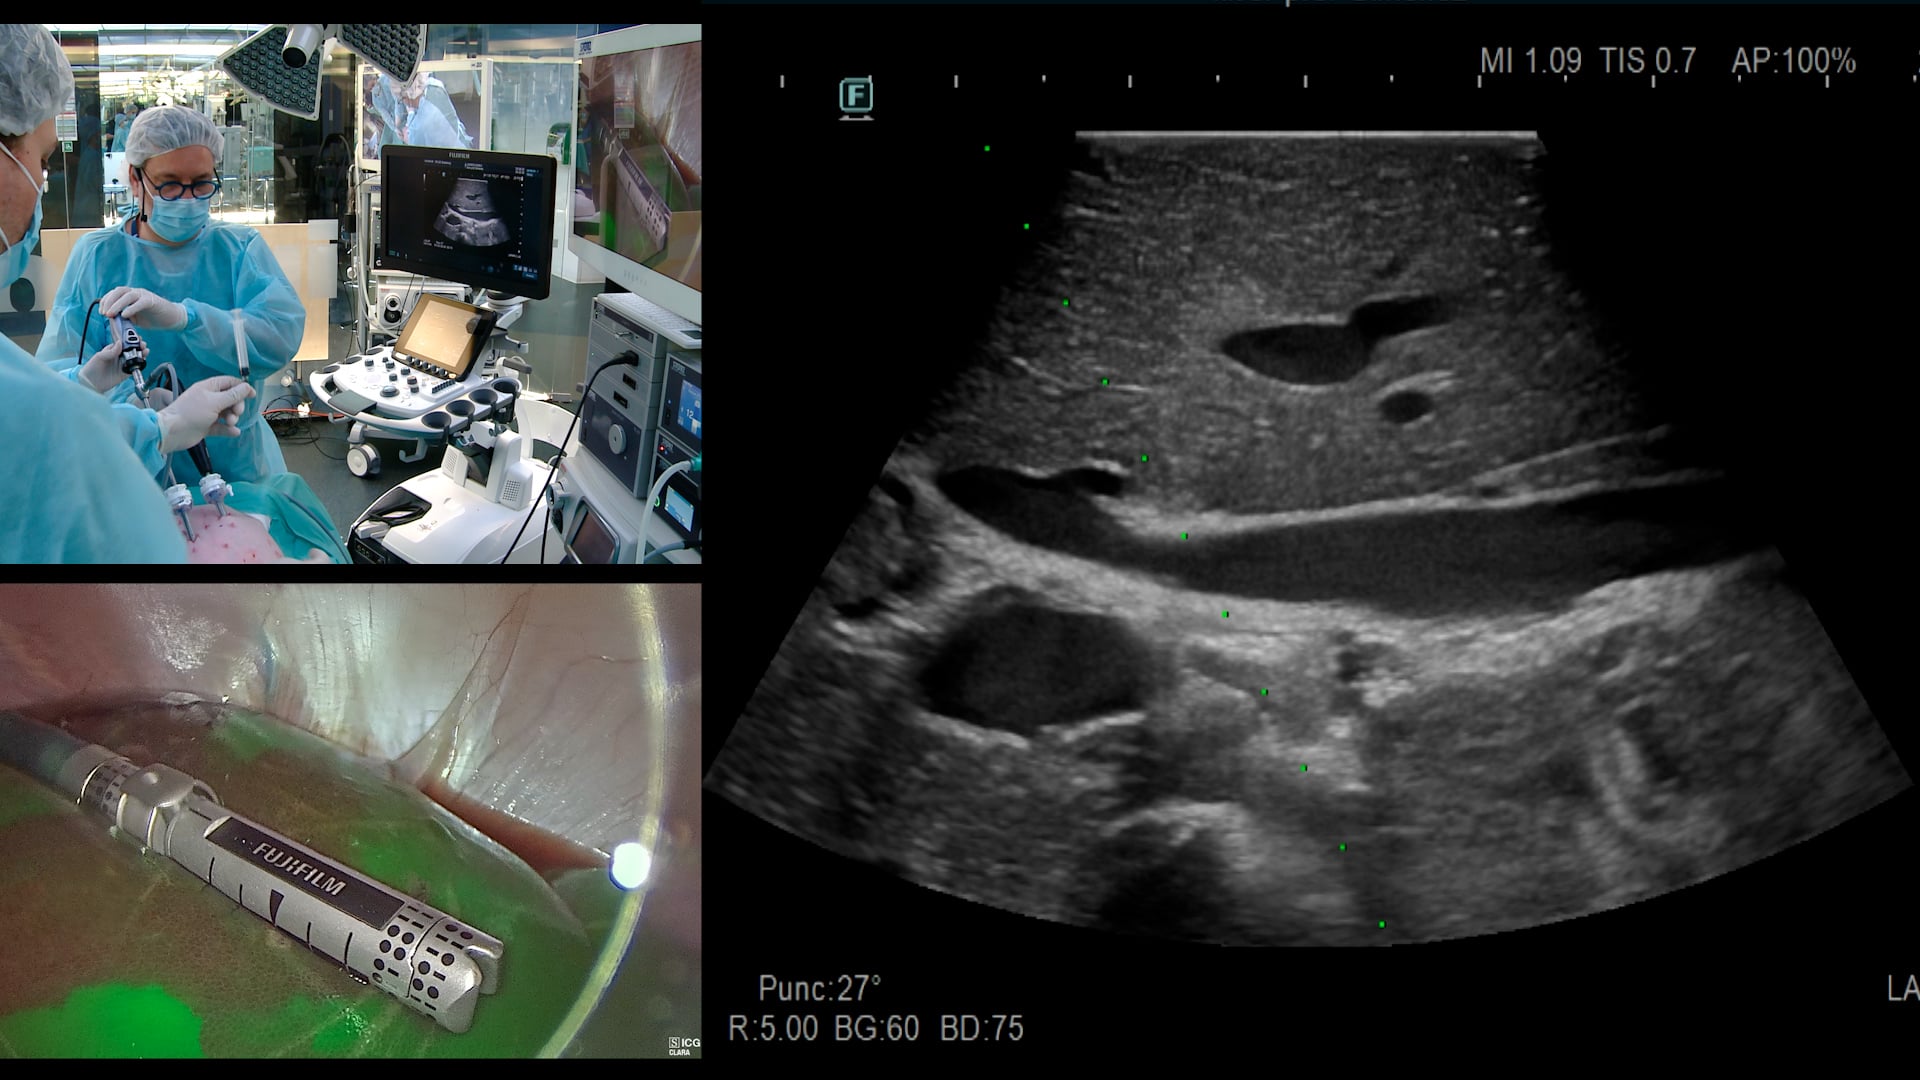

Latest on WebSurg

Exérèse totale du mésorectum (TME) robotisée avec section transanale et anastomose par agrafage circulaire : procédure live intégrale

Q Denost, B Noiret, A Forgione, D Kitaguchi

Résection antérieure laparoscopique avec excision totale du mésorectum avec imagerie par fluorescence et imagerie par contraste de tavelures laser (LSCI) pour évaluer la perfusion intestinale et l’application d’une matrice autologue de fibrine riche en plaquettes pour améliorer la cicatrisation anastomotique

L Baldari, A Forgione, L Boni, D Kitaguchi